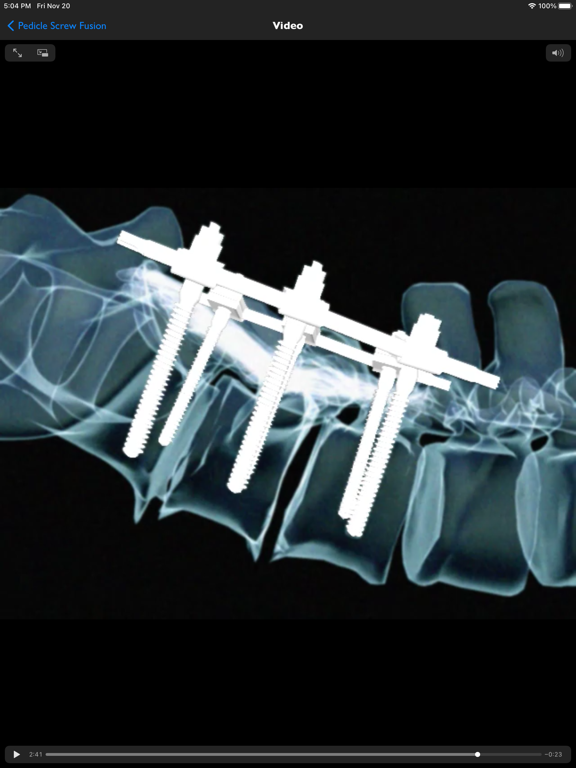

iSpineOperations is an information resource for common spine surgery procedures. It is a presentation library of surgical visualizations, medical images and educational notes. Whilst this app is primarily for clinicians providing patient education, it can also be useful to anyone who wants to know more about spine surgery goals and techniques.

iSpineOperations provides accurate spine surgery goal & technique visualizations for informed consent and education. Medical imaging shows real world examples and educational notes cover the indications, alternatives, expectations and complications.

- ALIF with bone+plate or cage, corpectomy with bone+plate, cage, cage+plate, pedicle screw fusion, PLIF with bone or cage, TLIF with bone or cage